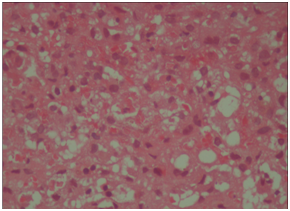

Upper endoscopy was done with normal results. Magnetic Resonance Cholangiopancreatography (MRCP) was done with the result of periportal and pericholecystic edema and decreased intrahepatic bile ducts diameter due to parenchymal hepatic edema. The other parts were normal according to the report (Figure 1).

Figure 1 Periportal and pericholecystic edema were found, the diameter of intrahepatic bile ducts was less than normal and pruned that could be due to parenchymal hepatic edema.